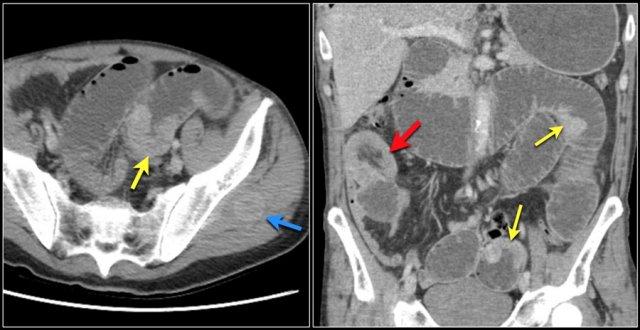

Đây là bệnh nhân u hắc tố di căn.

Hình bên trái cho thấy lồng ruột hồi-hồi do tổn thương di căn.

Hình bên phải cho thấy lồng ruột trên mặt phẳng coronal, cùng với một hạch bạch huyết mạc treo phì đại (mũi tên vàng) và di căn gan lan rộng.

Một bệnh nhân khác có tổn thương di căn ruột non.

Bệnh nhân này có tiền sử ung thư đại tràng và ung thư thực quản.

Bệnh nhân này có nhiều khối trong lòng ruột non (mũi tên vàng), được xác định là di căn từ u nguyên phát không rõ nguồn gốc.

Cũng lưu ý hình ảnh lồng ruột (mũi tên đỏ) và tổn thương di căn mô mềm ở cơ mông trái (mũi tên xanh lam).